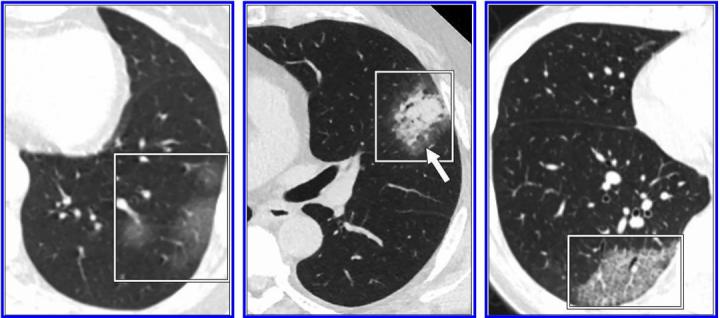

The specificity and positive predictive value of a laboratory test--in the case of COVID-19, reverse transcription-polymerase chain reaction (RT-PCR)--are based on its ability to limit false-positive findings. Acknowledging false-positive RT-PCR results are possible, Raptis, Henry, et al. maintained they are often caused by contamination and are likely insignificant in the setting of assays for COVID-19. CT, on the other hand, does not test for singular features unique to the disease, and even those features most characteristic of COVID-19 pneumonia--peripheral, bilateral ground-glass opacities typically in the lower lobes--have been reported in a number of other conditions, both infectious and noninfectious.

"At present," the authors of this AJR article concluded, "CT should be reserved for evaluation of complications of COVID-19 pneumonia or for assessment if alternative diagnoses are suspected."